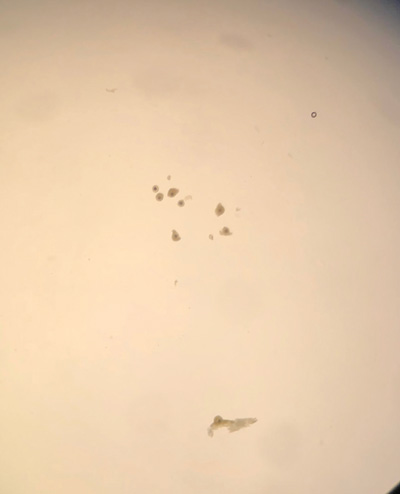

OPU involves trans-vaginal aspiration of all visible follicles on the ovary. OPU can be performed throughout the year as long as the mare has a sufficient number of follicles present (ideally at least 15 that are 10mm or above). Each follicle is entered and flushed individually while stabilising the ovary per rectum. The expected recovery rate is in the region of 50-60 per cent. This procedure is well tolerated with minor complications such as rectal irritation, fever, mild colic and mild peritonitis reported in < one per cent of procedures and major complications and death occurring rarely (approx. ~1:1,000 cases). The retrieved immature oocytes are then shipped overnight to an ICSI laboratory (Figure 1). At present oocytes are shipped to Avantea in Italy but we hope that in late 2022 we may be able to offer our own ICSI services here at UCD.

Figure 1: Oocytes obtained via OPU.